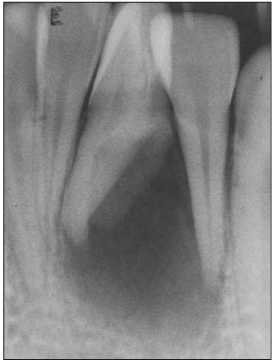

Figure 4

Master cone fitting and canal filling. Arrow indicates thinned dentinal wall.

Figure 4 Master cone fitting and canal filling. Arrow indicates thinned dentinal wall.